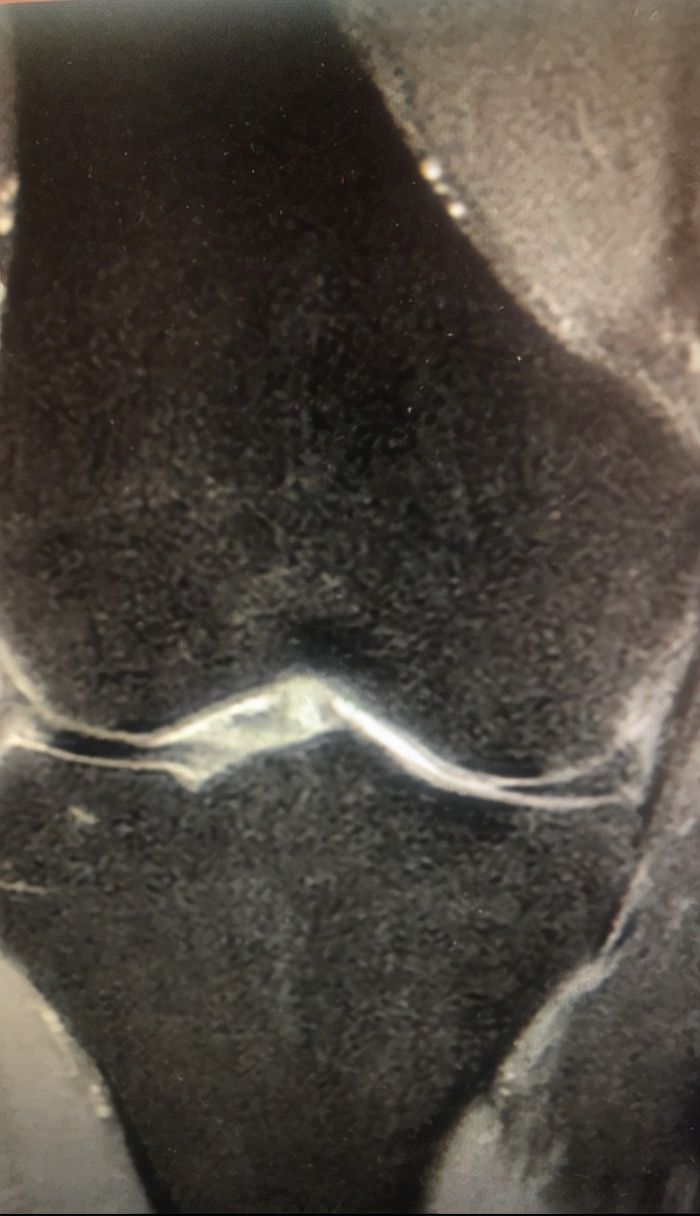

3个月前患者感觉双膝关节疼痛明显,并且双膝关节出现了肿胀,患者感正常生活受到了影响,夜间更是难以入眠,所以便在家人的陪同下来到我院就诊。根据患者自述的病史,门诊给予双膝关节MRI检查,综合考虑初步诊断为“双膝半月板损伤,双膝骨性关节炎”。为了进一步进行治疗,将患者收治入院。

为进一步了解患者双膝情况,对患者进行专科检查发现患者双膝关节压痛,双膝活动受限,范围为:0°-120°(完全伸直为0°),浮髌试验为阳性,麦氏征为阳性,下蹲试验为阳性,双下肢肌力尚可,感觉血运尚可,双侧足背动脉搏动良好。辅助检查MR检查结果显示患者双膝关节内侧半月板损伤周缘性位移并损伤(Ⅰ级),双膝关节退变并积液,左胫骨髁间隆突下、右胫骨内侧踝关节面下骨髓水肿,膝前皮下水肿、渗出,双膝关节内侧副韧带周围水肿、渗出,左膝关节交叉韧带粘液变性。

根据专科检查以及辅助检查结果,可以明确患者为双膝半月板损伤,双膝骨性关节炎,于是我针对患者情况采取对症治疗,消除关节水肿、渗出。经过两天的对症治疗,患者情况明显好转,一般情况尚可,由于家里原因,准许出院。